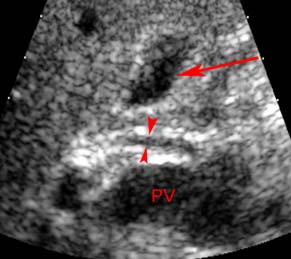

29.Cantisani V., Cantisani C. et al., (2010). Diagnotic imaging in the study of human hepatobiliary fascioliasis. Radiol med, (115), pp.83-92.

54.Ghanaei F. M., Alizadeh A., Pourrasoull Z. et al., (2006). Sonographic findings of human fascioliasis. Iran. J. Radiol, 4(1):11-15.

75.Kabaalioglu A., Ceken K., Alimoglu E., Saba R. et al., (2007). Hepatobiliary fascioliasis: Sonographic and CT findings in 87 patients during the initial phase and long-term follow up. AJR. (189):824-828.

85.Koc Z., Ulusan S., Tokmak N. et al., (2009). Hepatobiliary fascioliasis: Imaging characteristics with a new finding. Diagn Interv Radiol, (15):247-251.

131.Richter J, Freise S, Mull R, Millan JC, (1999). Fascioliasis: Sonographic abnormalities of the biliary tract and evolution after treatment with triclabendazole. Trop Med Int Health 4:774-781.

145.Taheri M.S., Aminzade Z., Shokohi S. et al., (2007). Hepatobiliary fascioliasis: Clinical and radiological features. Iranian J Parasitol, 2(4):48-55.

164.Yesildag A., Yildiz H., Demirci M., et al., (2009). Biliary fascioliasis: Sonographic appearance patterns. Journal of Clinical ultrasound, 37(1):26-30.

165.Yesildag A., Senol A., Koroglu M., Kockar C., et al., (2010). Hepatobiliary fascioliasis: A case with unusual radiological features. Diagn Interv Radiol, vol (16):299-301.